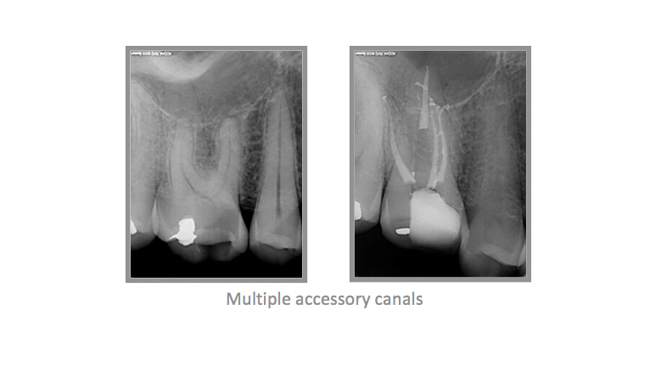

• A few Teeth Treated by Dr. Katsarsky